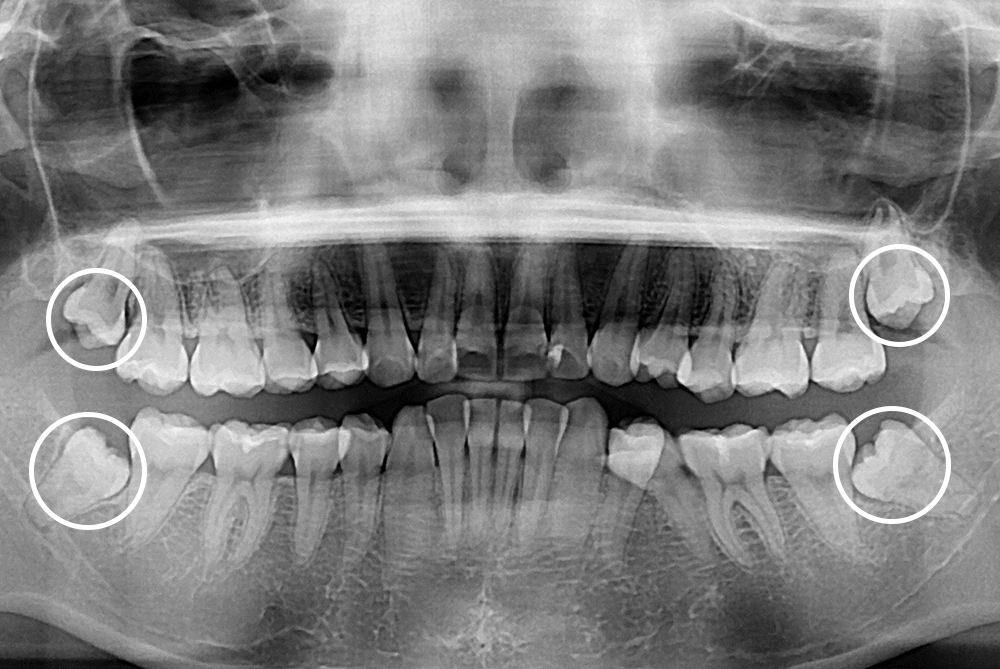

[사랑니] 매복 사랑니 발치

치료전 : 2015-10-20